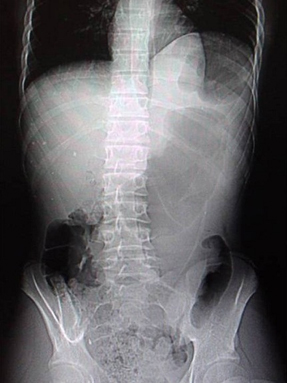

Image radiologie ASP de face

une volvulus de estomac est image de elevation du

diapragme droit avec de distention gastrique marquee |